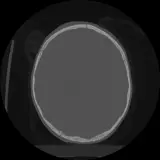

Over 2,100 interactive radiology cases, curated by radiologists for your level of training. Scroll, window, and view cases full screen โ€” just like on PACS. Click linked findings in each writeup to jump straight to them on the image. Cases include sample reports, a focused discussion section, original illustrations, and videos.

PACS์—์„œ ๊ธฐ๋Œ€ํ•  ์ˆ˜ ์žˆ๋Š” ๋ชจ๋“  ๋„๊ตฌ๋ฅผ ๊ฐ–์ถ˜ ์™„์ „ํ•œ ์ธํ„ฐ๋ž™ํ‹ฐ๋ธŒ ์ฆ๋ก€ — ์Šคํฌ๋กค, ์œˆ๋„์šฐ ์กฐ์ ˆ, ํ™•๋Œ€/์ถ•์†Œ, ํŒจ๋‹, ๊ณ„์ธก, ROI, ์ „์ฒด ํ™”๋ฉด ๋ชจ๋“œ๊นŒ์ง€ ์ง€์›ํ•ฉ๋‹ˆ๋‹ค.

์ฃผ์š” ์†Œ๊ฒฌ์„ ์ฆ๋ก€์— ์ง์ ‘ ํ‘œ์‹œํ•˜๋Š” ํ’๋ถ€ํ•œ ์ฃผ์„์ด ํฌํ•จ๋˜์–ด ์žˆ์Šต๋‹ˆ๋‹ค. ์ฆ๋ก€ ์„ค๋ช…์˜ ์—ฐ๊ฒฐ๋œ ์†Œ๊ฒฌ์„ ํด๋ฆญํ•˜๋ฉด ์Šค์บ” ๋‚ด ์ •ํ™•ํ•œ ์œ„์น˜๋กœ ๋ฐ”๋กœ ์ด๋™ํ•ฉ๋‹ˆ๋‹ค.

์–ด๋ ค์šด ์ฆ๋ก€๋ฅผ ์ •ํ™•ํžˆ ํŒ๋…ํ•˜๋Š” ๋น„๊ฒฐ์€ ๋Œ€๊ฐœ ์œ ์‚ฌํ•œ ์ฆ๋ก€๋ฅผ ์ด์ „์— ๋ณธ ์ ์ด ์žˆ๋Š”์ง€์— ๋‹ฌ๋ ค ์žˆ์Šต๋‹ˆ๋‹ค. ํฌ๊ด„์ ์ธ ์ง„๋‹จ ๋ชฉ๋ก์„ ์•„์šฐ๋ฅด๋Š” 1,900๊ฐœ ์ด์ƒ์˜ ์—„์„ ๋œ ์ฆ๋ก€๋กœ ์—ฐ์Šตํ•˜์„ธ์š”.